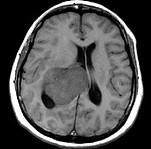

问题 女,45岁,右眼视力下降8个月,右颜面麻木半个月,时有头昏,味觉减退,请根据所提供图像,选择最可能的诊断()

选项 A.(右侧脑室)脑膜瘤(合体细胞型) B.(右侧脑室)室管膜瘤 C.(右侧脑室)脉络膜乳头状瘤 D.(右侧脑室)胶质瘤 E.(右侧脑室)转移瘤

答案 A